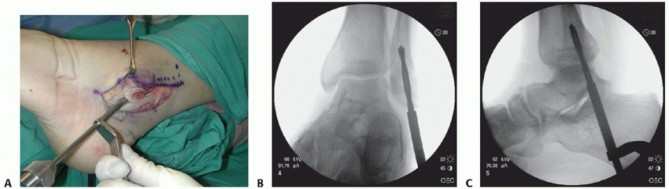

| Chronically dislocated peroneal tendons may create a new pocket and even gliding surface on the lateral fibula (TECH FIG 7). | |||

| From the distal fibular tip, introduce progressively larger diameter drill bits to weaken the distal fibula and ream away the distal fibular cancellous bone (TECH FIG 8). | |||

| The peroneal tendons should remain reduced without manually restraining them (TECH FIG 10A). If not, then deepen the groove further with a larger diameter drill bit and perform further impaction of the posterior fibular surface. | |||

| Reattach the SPR to the posterolateral fibular margin via drill holes. | |||

| Be sure the peroneal tendons glide well without restriction in the deeper fibular groove (TECH FIG 10B). Standard closure | |||